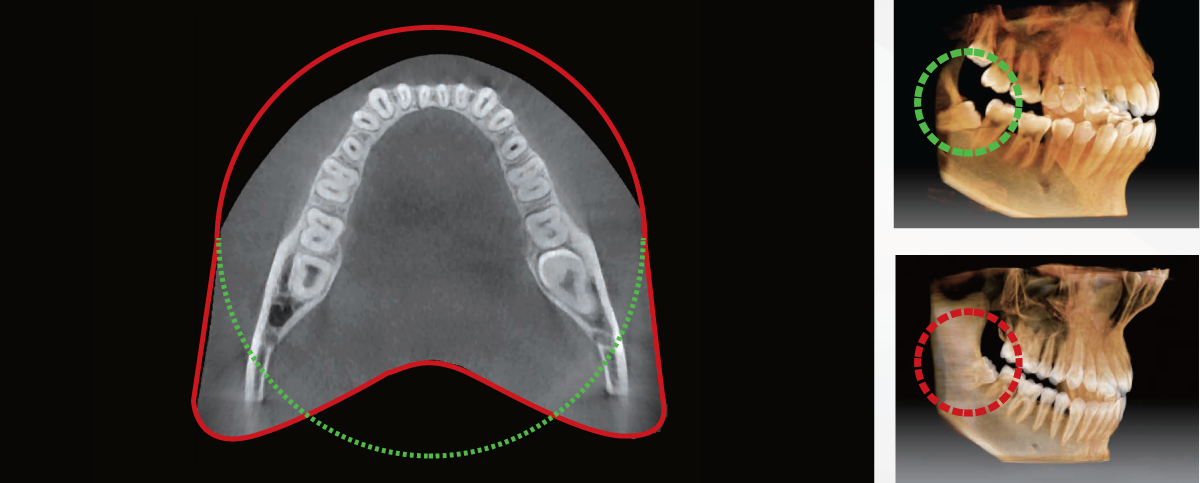

EXTENDED ARCH SHAPED ANATOMICAL FOV (12x9cm)

The innovation FOV of the Smart Plus provides an arch-shaped volume, which shows a wider view of the dentition compared to other devices of the same FOV. When a tooth is lying on its side, there is a high possibility that the tooth will be cut out of the image. The “arch-shared volume” eliminates this possibility and shows the hidden dentition area.